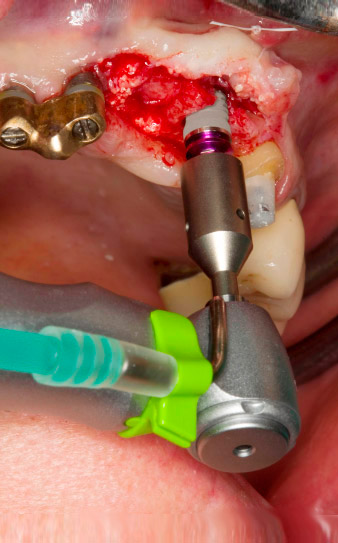

Der Alveolarknochen erweist sich an Position 22 als ausreichend dimensioniert. Die Abbildungen 2 und 4 zeigen die Implantatbett-Aufbereitung, den Gewindeschnitt und die Implantation mit dem Implantmed.

Gewindeschnitt mit dem Winkelstück WS-75 L

Abb. 3: Gewindeschnitt mit dem Winkelstück WS-75 L bei einer Übersetzung von 20:1 (Programm P4). Hilfreich sind hier das hohe Drehmoment des Implantmed, das Hexagon-Spannsystem für sichere Kraftübertragung und die automatische Umkehr der Drehrichtung bei zu hohem Widerstand.

Maschinelles Eindrehen des Implantats

Abb. 4: Maschinelles Eindrehen des Implantats mit dem Winkelstück WS-75 L bei einer Übersetzung von 20:1 (Programm P5).